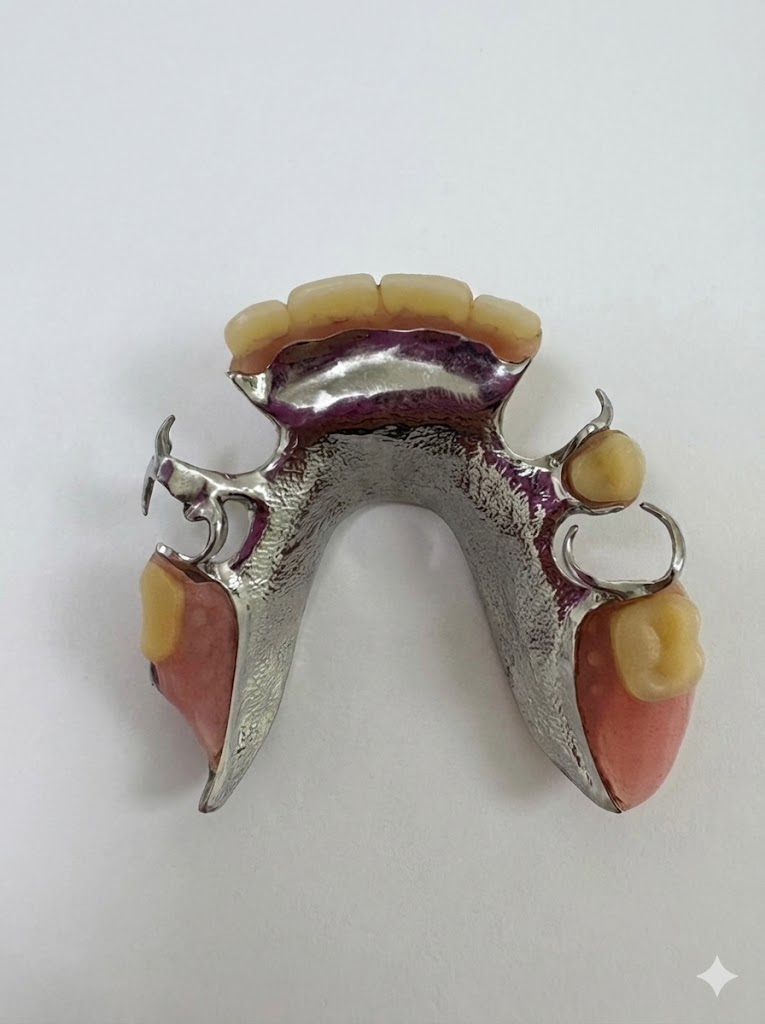

今回使用したのは、精密性が高いコーヌステンチャー(ロケーター義歯よりも精密)。

【コーヌスデンチャー】

今回採用した「コーヌステンチャー」は、

■フィット感が非常に高い

■安定性に優れている

という点が大きなメリットです。

ロケーター義歯のように着脱のしやすさを重視したタイプもありますが、

精密な噛み合わせや長期の安定性を求める場合には、コーヌスが適している ケースも多くあります。